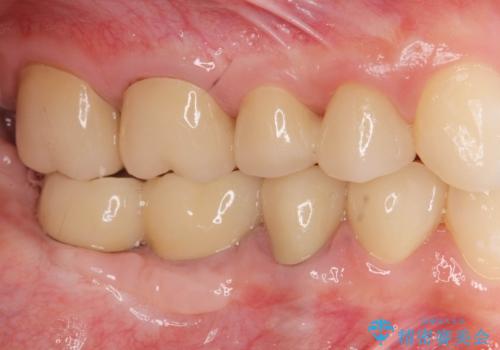

遊離歯肉移植術を伴うインプラント治療

また、機能後のインプラント周囲の清掃性を高めるため遊離歯肉移植術を行っています。

インプラント周囲に強固な歯ぐきを移植することで、歯ブラシがしやすくなりインプラント周囲炎対策となります。